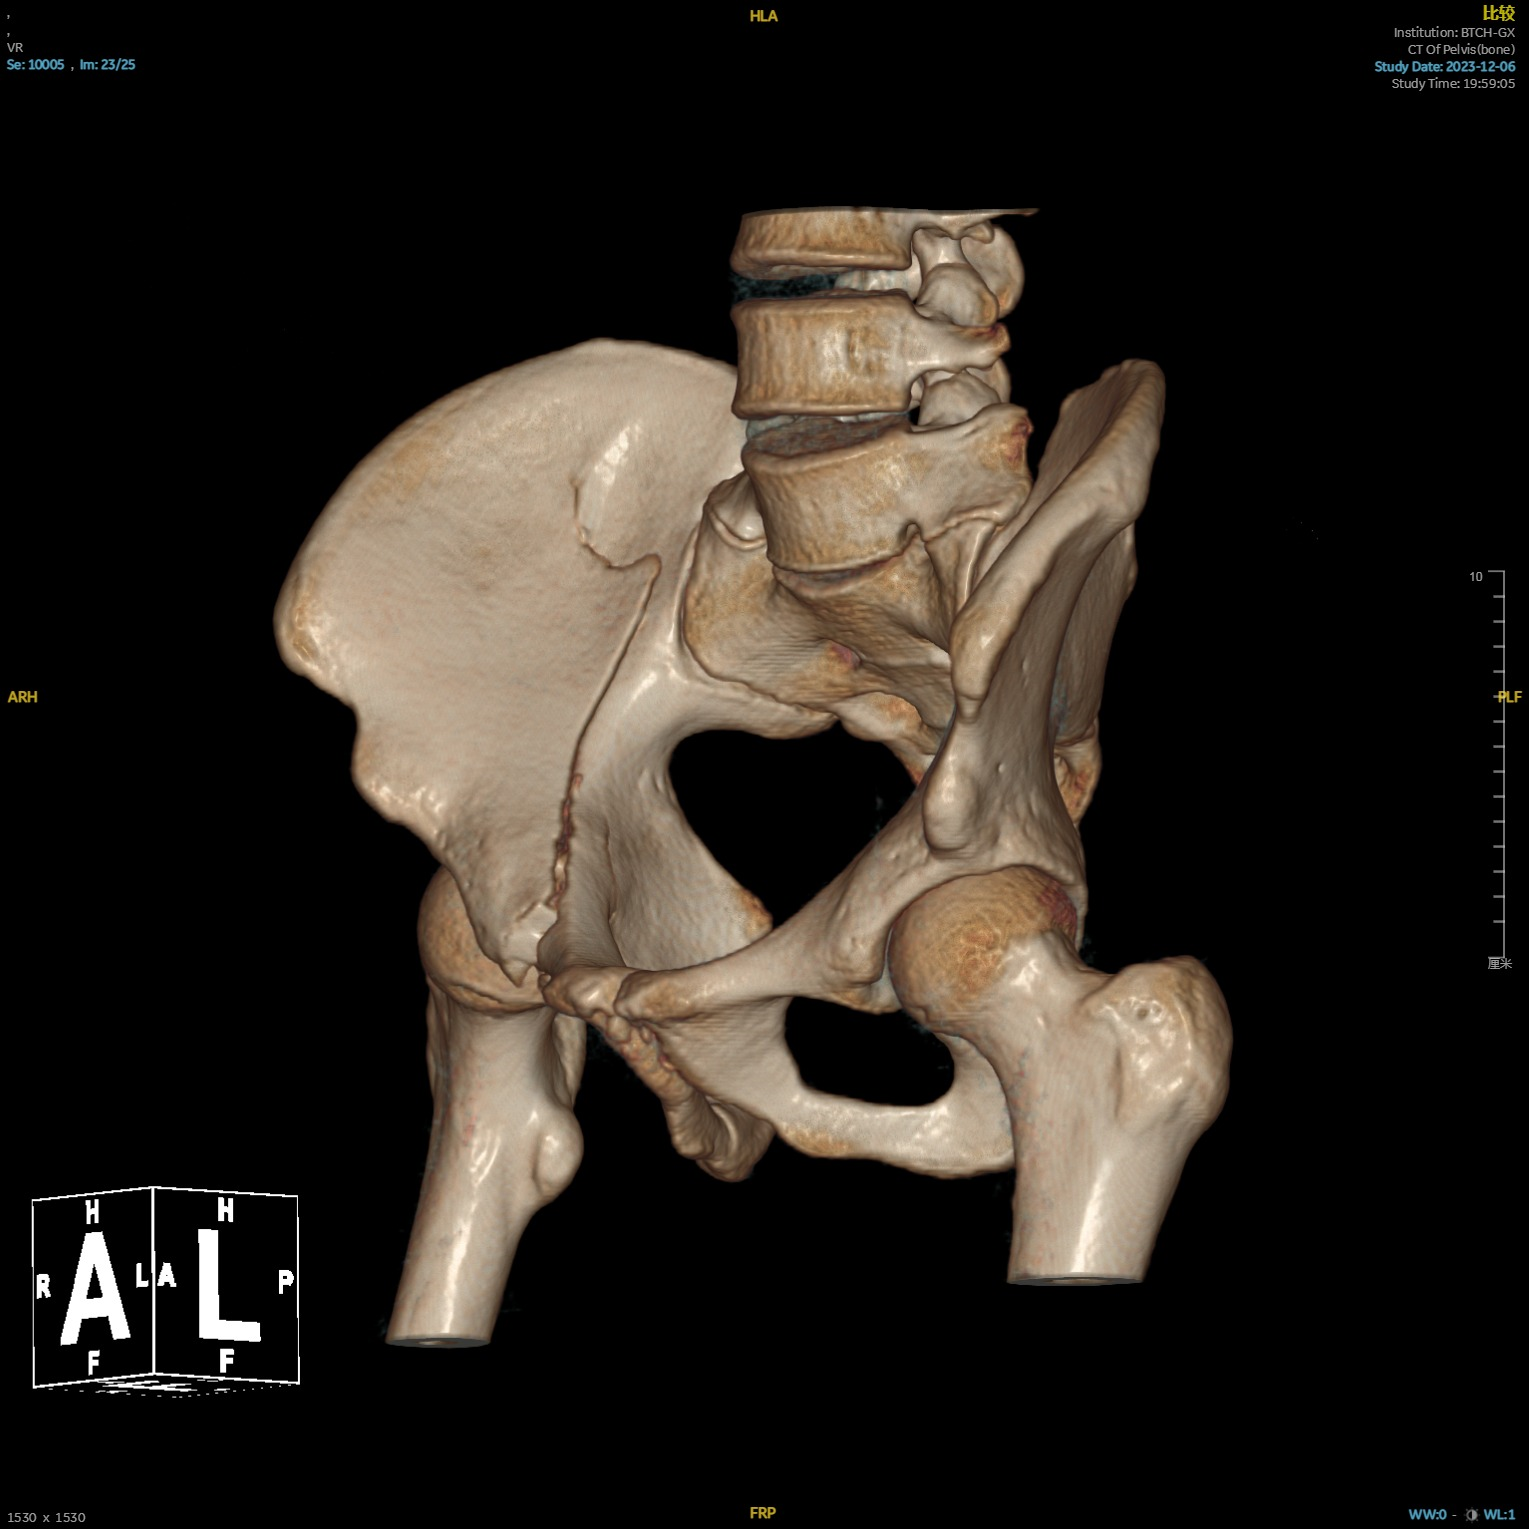

本次手术患者20岁,骑电动车时不幸发生车祸,导致其右侧髋部、左侧踝关节疼痛,随后来到北京清华长庚医院急诊就诊。经检查,患者被诊断为右侧髋臼骨折、右侧髂骨骨折、左侧踝关节骨折。

术前影像1.png  术前影像2.png  术前影像3.png

患者多处骨折影像资料